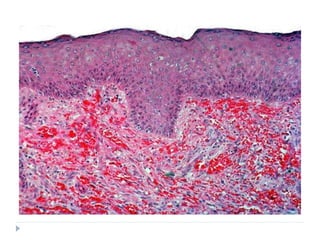

 Patch stage:

 Proliferation of small veins and capillaries around pre-

existing dilated vessels

 Slit-like vessels are seen which are lined by plump, mildly

atypical endothelial cells

 Scattered erythrocytes and hemosiderin deposits are

seen

 Perivascular spindle cell proliferation with minimal cellular

atypia